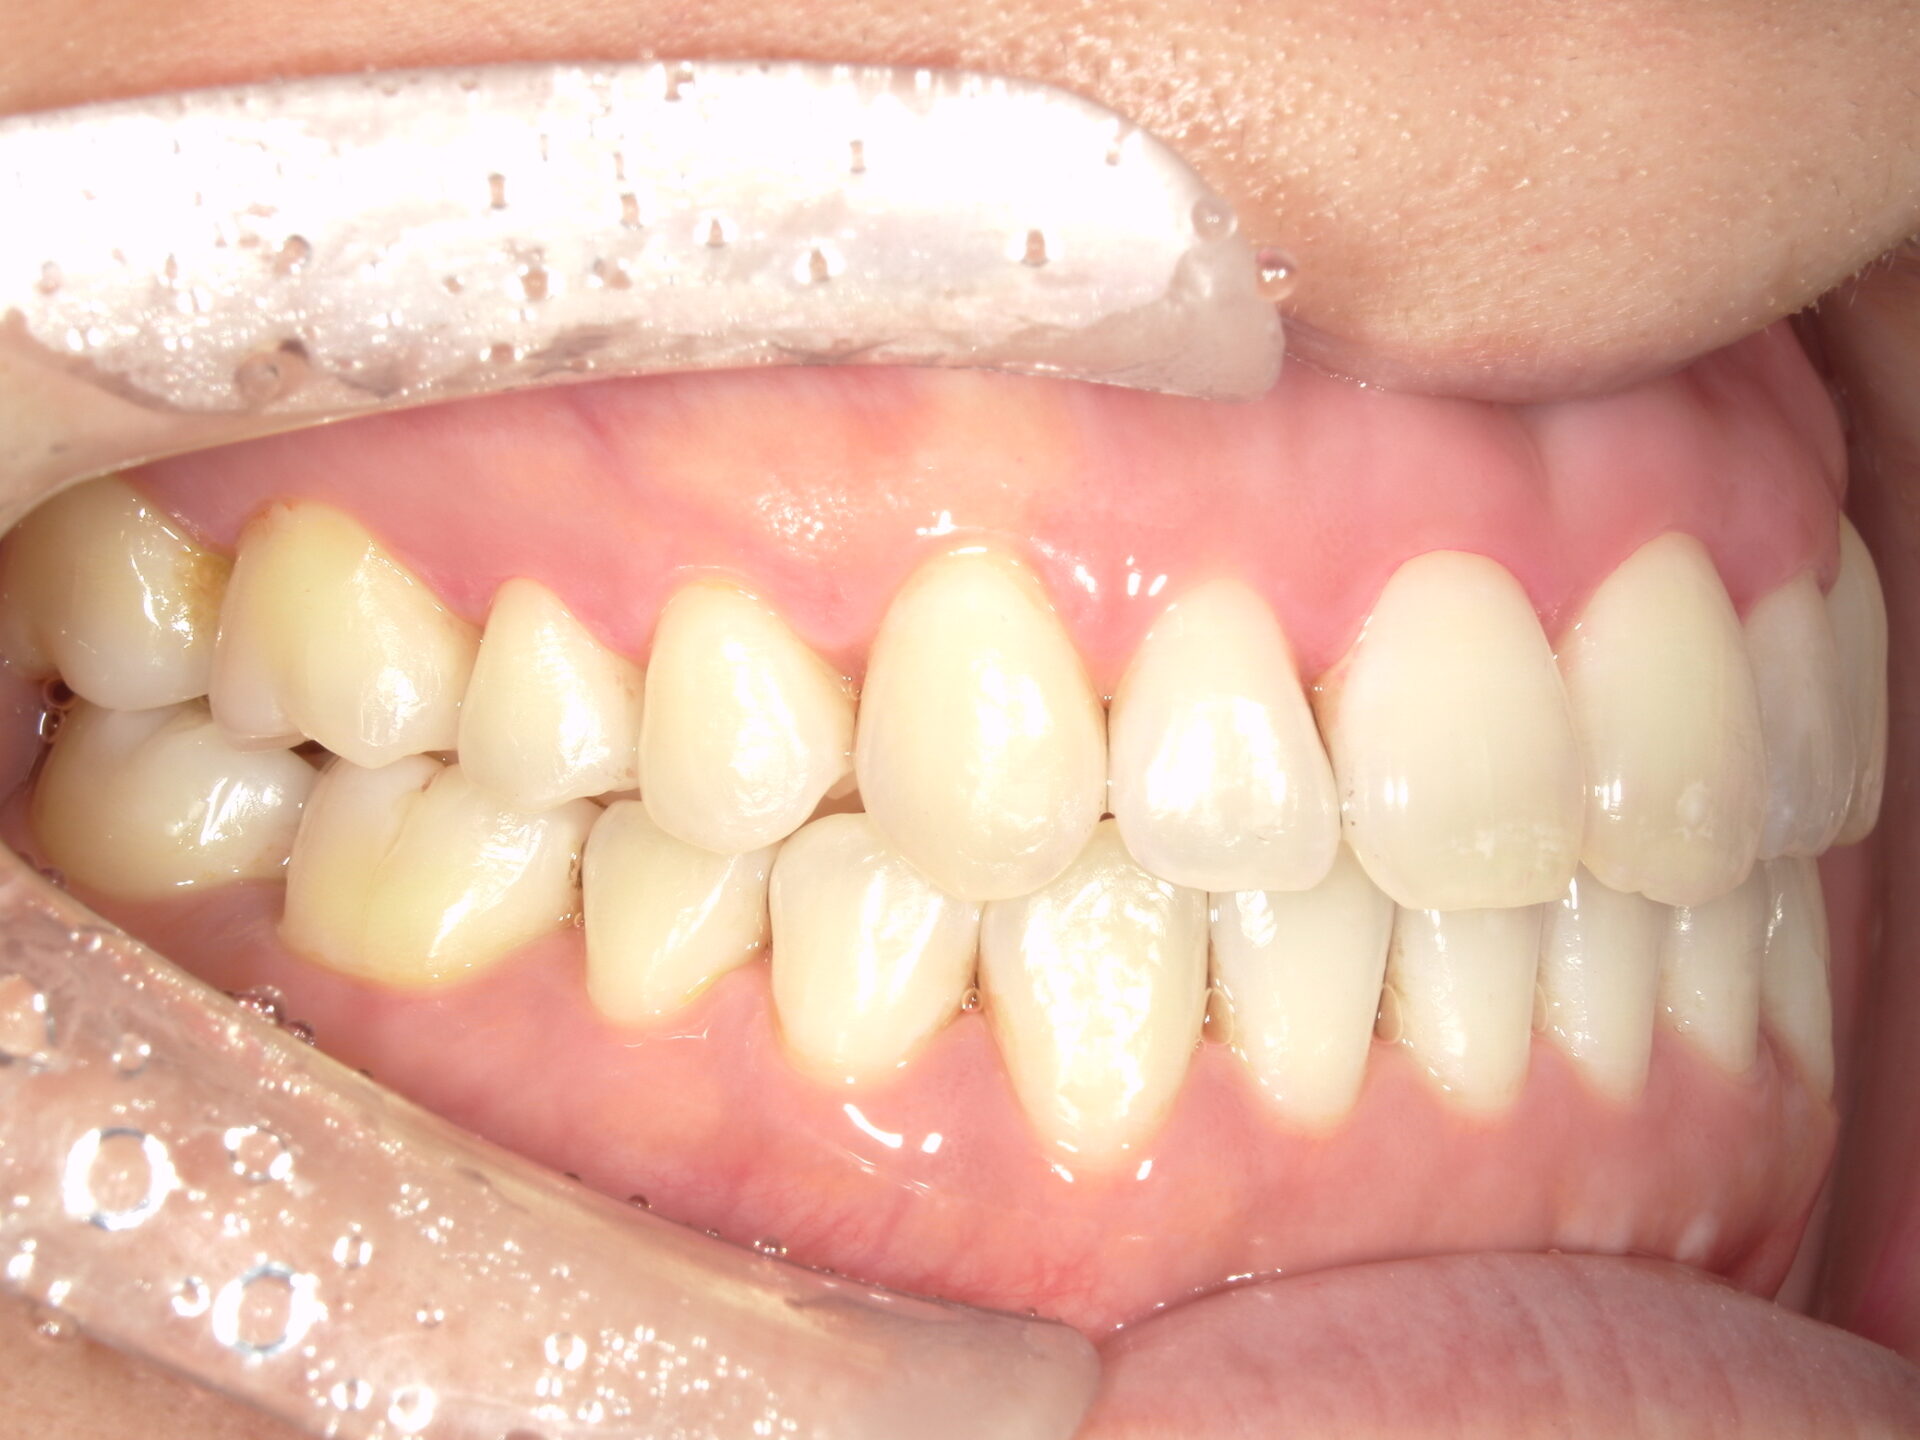

before

患者さんの年齢 20代 女性 症状 ガタガタを治したい 治療内容 マウスピース矯正治療 費用 90万(税抜) 治療期間・回数 治療期間2年、通院回数10回 メリット 笑顔が綺麗 デメリット・リスク 期間がかかることがある - マウスピース矯正